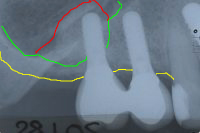

In den Abb. 4 bis 6 ist der Vorgang des Sinuslifts anhand dreier Röntgenbilder selbsterklärend dargestellt.